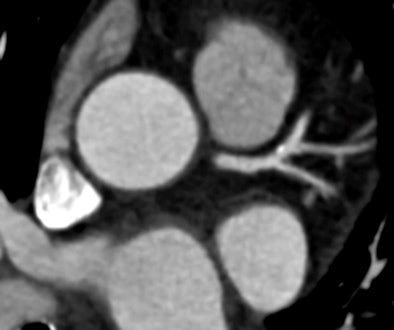

| Compared with filtered back projection reconstruction (above), use of the TRIM algorithm improves temporal resolution and renders a more diagnostic image. Images courtesy of Dr. U Joseph Schoepf, MUSC. |

"Despite cardiac CT image acquisition with slower gantry rotation, the temporal resolution improved reconstruction algorithm evaluated here provided more diagnostically adequate image quality for coronary artery assessment than the standard FBP [filtered back projection] reconstruction algorithm," wrote Dr. Paul Apfaltrer from the University of Heidelberg and MUSC, and colleagues in an article-in-press in the European Journal of Radiology (November 5, 2012).